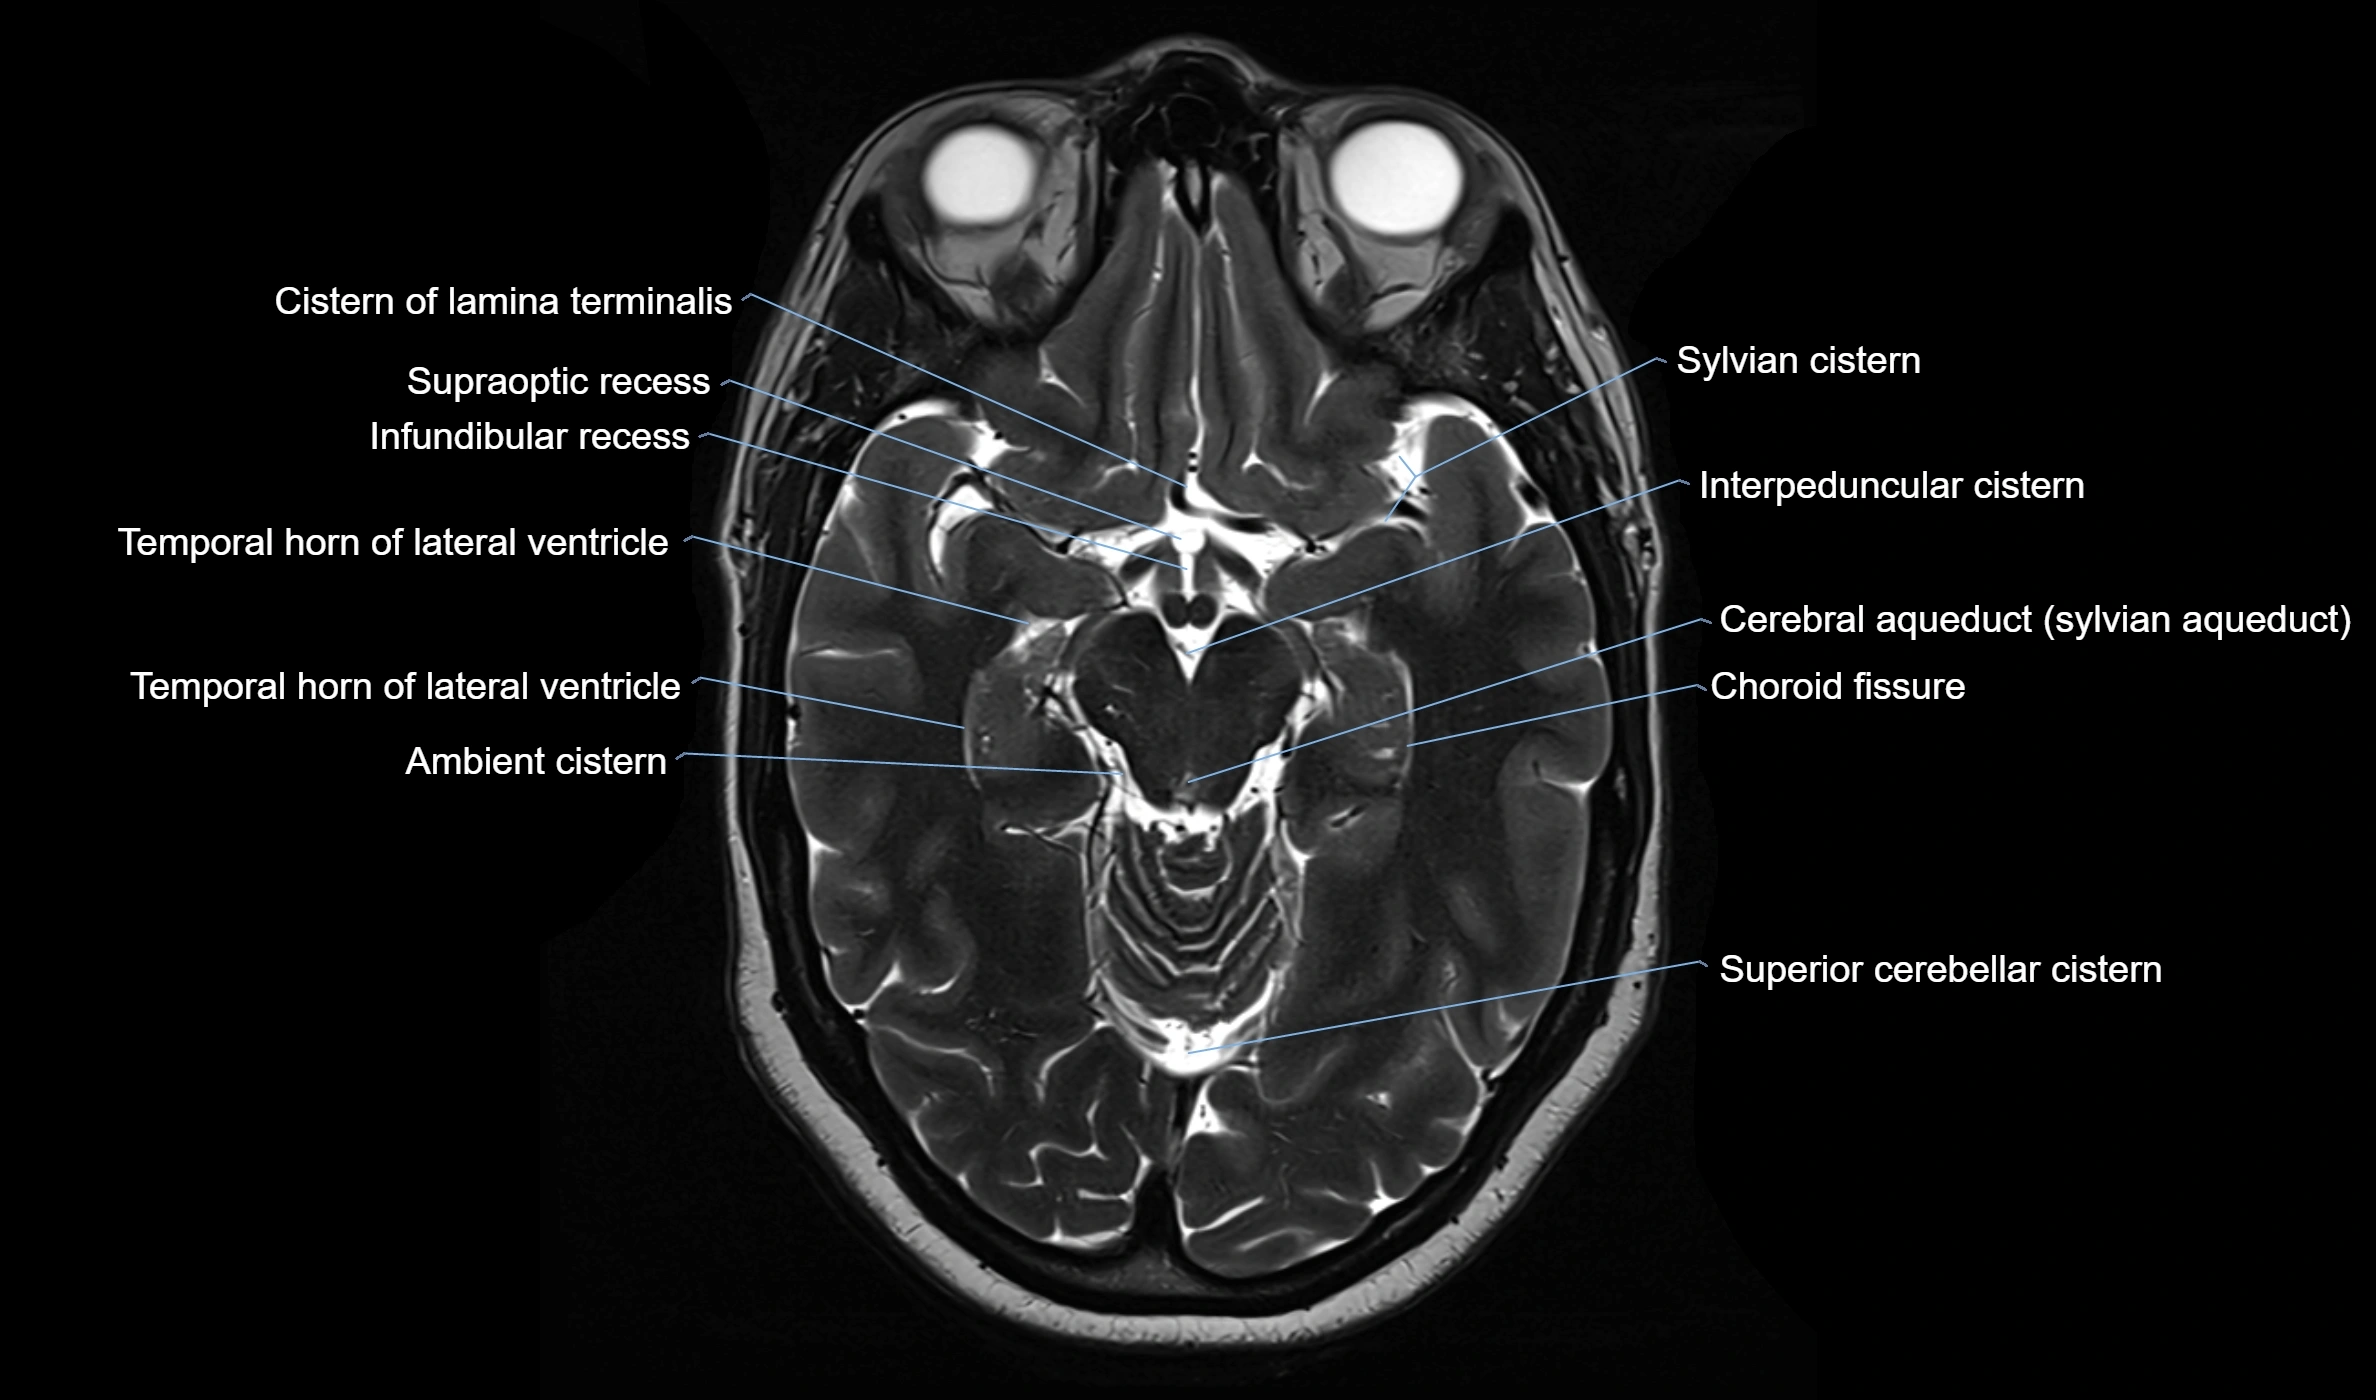

Ambient cistern

The ambient cistern is a paired, narrow, and elongated subarachnoid space located bilaterally along the lateral aspect of the midbrain. It serves as a conduit between the interpeduncular cistern anteriorly and the quadrigeminal cistern posteriorly. This cistern houses critical neurovascular structures, including parts of the posterior cerebral artery, superior cerebellar artery, trochlear nerve (cranial nerve IV), and the basal vein of Rosenthal. It plays an important role in the circulation of cerebrospinal fluid (CSF) and provides an anatomical corridor for various vessels and nerves passing around the midbrain.

MRI Appearance

• T2-weighted images:

• The cistern is hyperintense (bright) due to the high water content of CSF.

• Encapsulated vessels and nerves are seen as flow voids or hypointense lines within the bright background.

MRI images

image